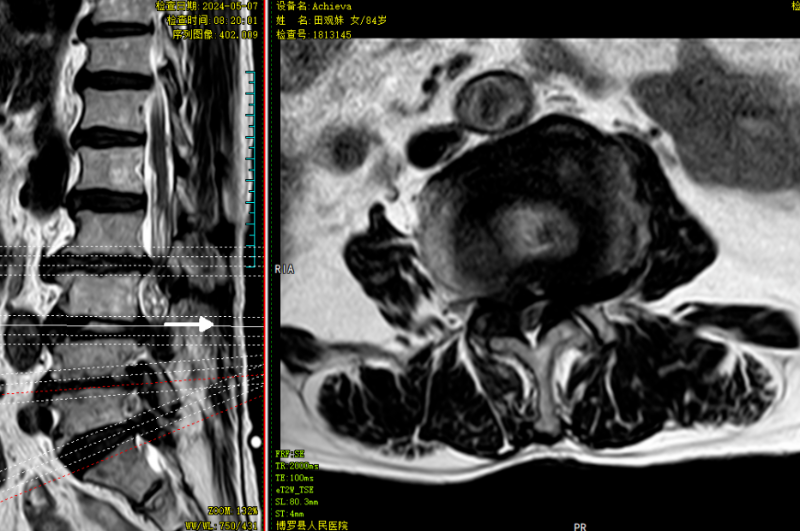

△術前MR可見腰3/4、腰4/5椎間盤突出,伴椎管狹窄嚴重、神經根受壓、馬尾神經冗余。